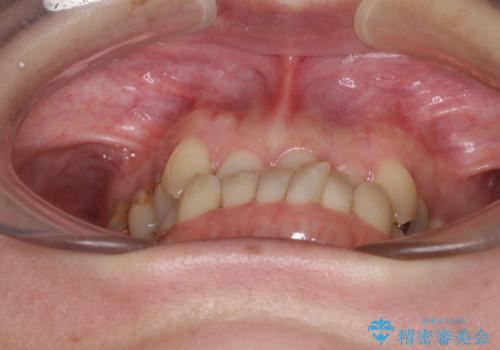

急速拡大装置 前歯の反対咬合をインビザラインで改善

- 前歯の反対咬合を気にして来院された患者様です。

上顎骨の幅が下顎骨よりも小さいので、拡大装置により骨幅を広げて上下関係を改善すると同時にワイヤー矯正で反対咬合の改善を図り、その後インビザラインにて歯並びを整えることとしました。

上顎前歯の矮小歯は矯正治療の途中でオールセラミッククラウンを装着し、左右のバランスを整えることとしました。

急速拡大装置の使用により奥歯の咬み合わせが劇的に変わり、その変化を利用して反対咬合を改善することができました。

治療期間中は奥歯が咬み合わず、食事が取りにくいなどの不都合がありましたが、最終的にはきれいに整えることができました。